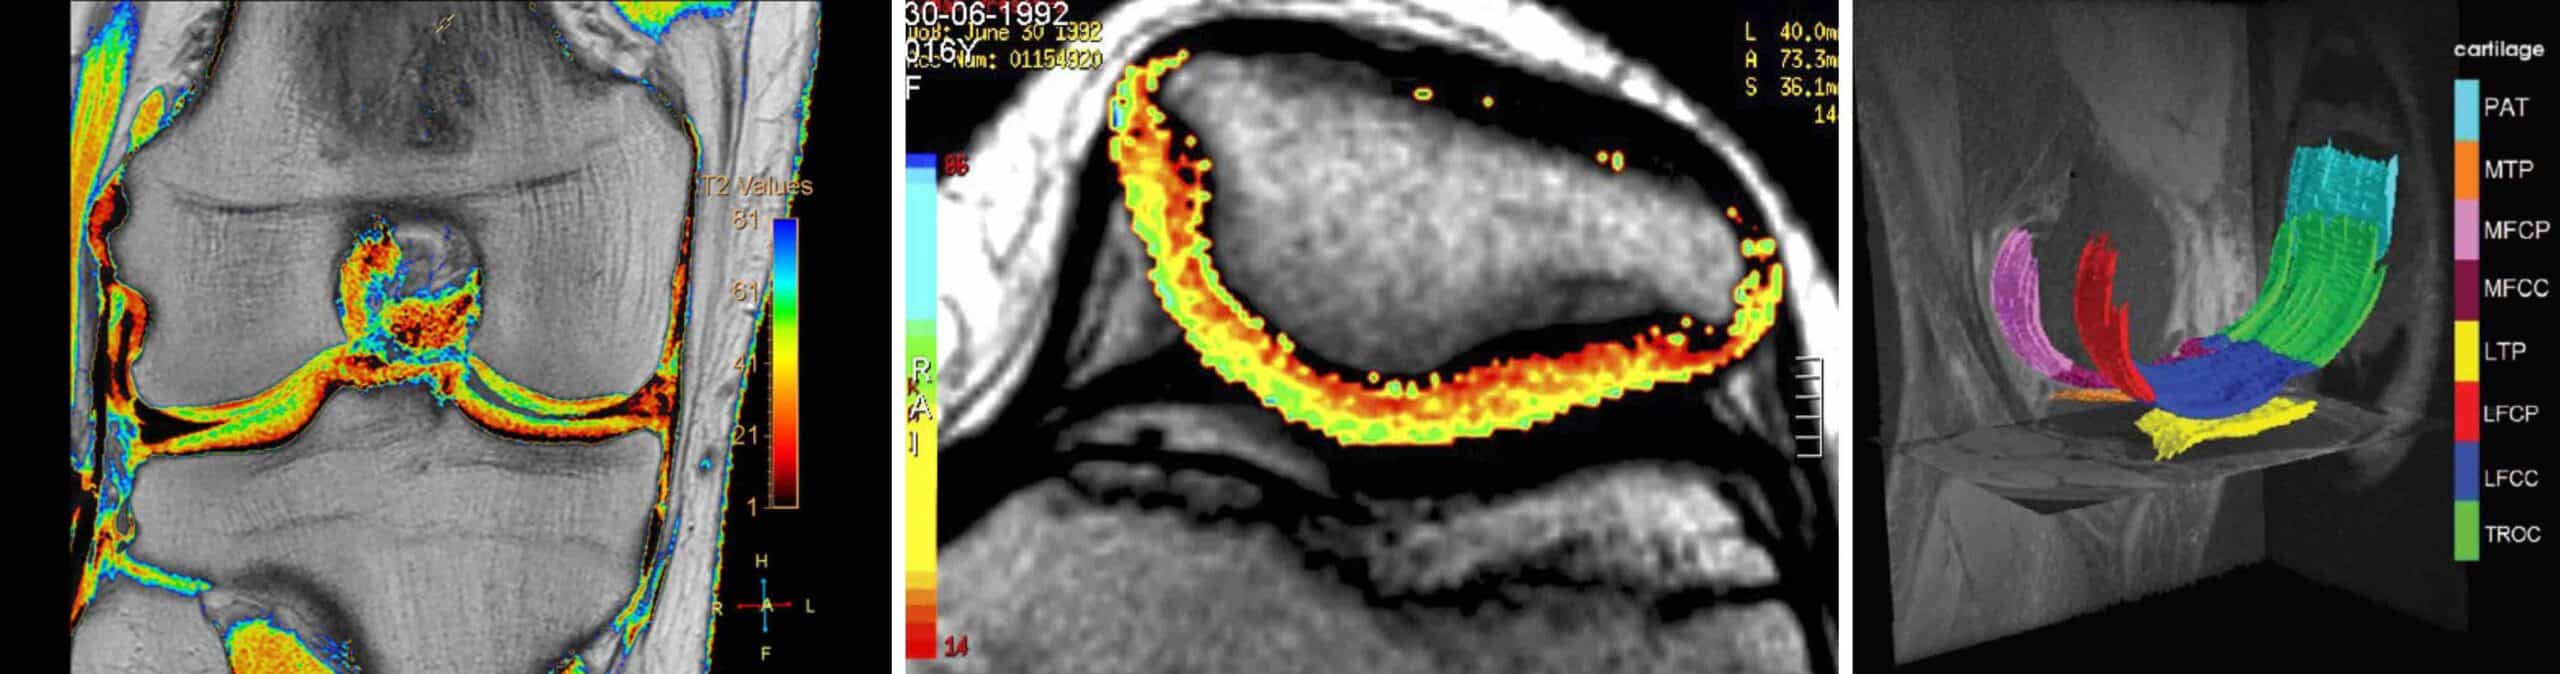

Condrometria do joelho é um exame moderno e não invasivo utilizado para avaliar a espessura e a integridade da cartilagem. O objetivo da condrometria do joelho é avaliar quantitativamente o grau de desgaste ou perda da cartilagem. A condrometria pode ser feita através do exame de ressonância magnética do joelho ou através da artroscopia do joelho. A partir dos dados da condrometria feita pelo exame de ressonância magnética do joelho é possível fazer o cartigrama, que é um mapa visual colorido que mostra a distribuição e a espessura da cartilagem na articulação. O cartigrama é a representação gráfica da condrometria.

Condrometria do joelho é um exame utilizado para avaliar a integridade da cartilagem da articulação. A palavra condrometria vem dos termos “chondro” ( cartilagem ) e “metria” ( medição ), ou seja, significa medição da cartilagem. O exame analisa a espessura, o volume e a qualidade articular patelofemoral, femorotibial e meniscal, identificando alterações antes que causem danos permanentes. A condrometria representa um avanço significativo na ortopedia e na medicina esportiva. Por meio da condrometria é possível identificar o desgaste da cartilagem do joelho nas suas fases iniciais, permitindo tratamentos menos invasivos, mais precoces e mais eficazes. A condrometria do joelho é um exame fundamental para prevenir a progressão da artrose e garantir a longevidade articular. Trata-se de uma nova ferramenta que já se tornou essencial para o diagnóstico precoce dos problemas da cartilagem do joelho.

O método mais utilizado para se fazer a condrometria do joelho é através do exame de ressonância magnética. Essa técnica é também conhecida como ressonância condral. Sequências específicas do exame de ressonância magnética mapeiam a cartilagem do joelho e detectam alterações estruturais microscópicas antes mesmo de aparecerem nas sequências convencionais. A condrometria detecta alterações fisiológicas na cartilagem relacionadas à sua composição bioquímica. A partir dos dados da condrometria o computador monta o cartigrama, que é a representação gráfica colorida da cartilagem do joelho. No cartigrama a cartilagem é mapeada com diferentes cores que evidenciam mudanças sutis na ultraestrutura condral.